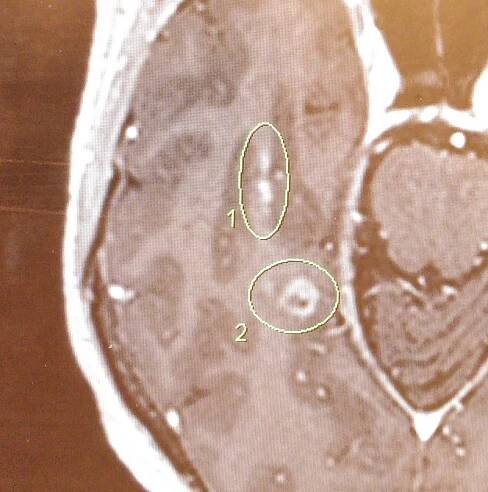

Endoparazit je označení pro parazitický organizmus, která žije uvnitř svého hostitele. Žije-li parazit na povrchu hostitelova těla, pak hovoříme o ektoparazitovi.

Endoparazit je cizopasník, který žije uvnitř těla hostitele. Konkrétními příklady endoparazitů jsou různé druhy parazitických červů a parazitických prvoků. Odvozená ...

Parazit, jehož celé tělo nebo jeho valná část je v buňkách nebo mezi buňkami hostitele (intracelulární respektive intercelulární parazit),